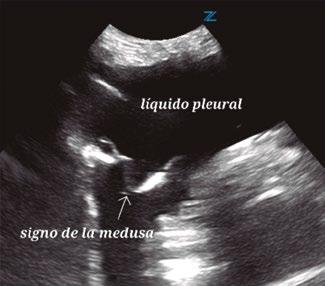

Utilidad de la ecografía cardiaca y pulmonar en urgencias

Utilidad clínica de la ecografía pulmonar y cardiaca en urgencias